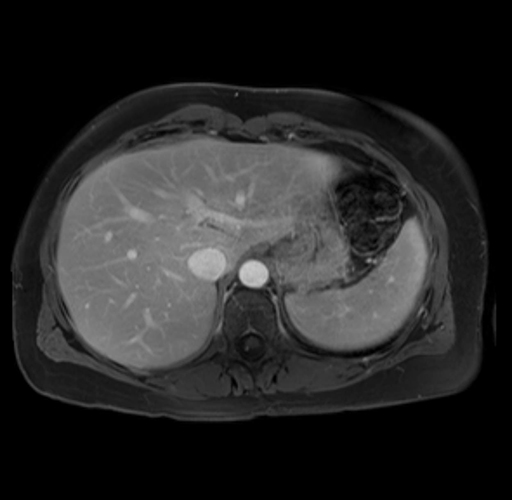

Imaging Analysis

Look through the patient's CT scan to identify any areas of concern for the necessary procedure.

Based on your CT findings, which issue(s) are present and would give reason for "planned slowing down moment(s)" in this case?

Considering a standard distal pancreatectomy procedure, what step(s) of the operation would you do differently in this case?